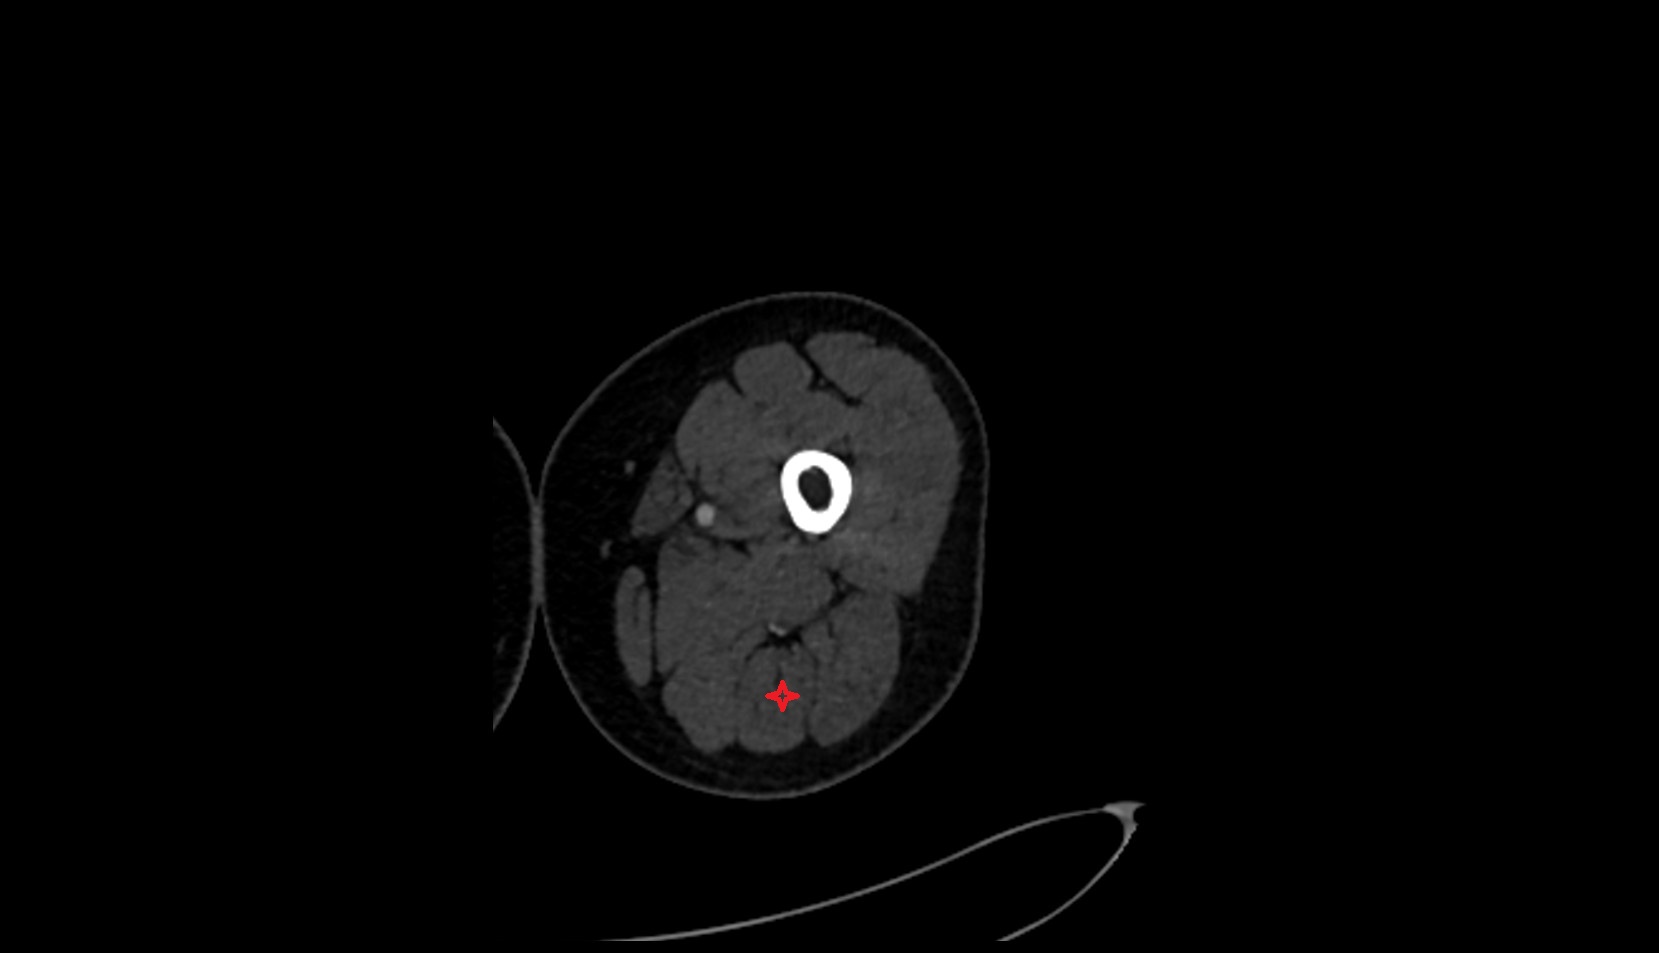

- Placenta

- Uterus (pregnancy)

- Amniotic fluid

- Umbilical cord

- Urinary Bladder in Pregnancy

- Cervix in Pregnancy

- Vagina in Pregnancy

- Fundus of uterus in pregnancy

- Fetal brain

- Fetal lateral ventricle